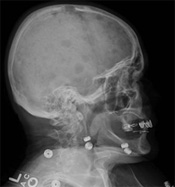

Dentists and oncologists both are now using X-rays to detect “ghost sockets” among patients who take bisphosphonates. The appearance of a ghost socket indicates improper healing in the jawbone and early detection of a ghost socket can prevent permanent damage from occurring, according to an article in the March/April 2009 General Dentistry, the Academy of General Dentistry’s (AGD) clinical, peer-reviewed journal.

A ghost socket appears when the jawbone is not healing and repairing itself correctly. Kishore Shetty, DDS, MS, MRCS, lead author of the article reports “The good news is that even though these ghost sockets may occur, by using radiographic techniques we can see that the soft tissue above these sockets can still heal.” Shetty is also vigilant in pointing out that early prevention and detection are essential for avoiding permanent damage.

Bisphosphonates are a staple in the armamentarium used to prevent and treat osteoporosis, multiple myeloma, Paget’s disease (bone cancers), and bone metastasis from other cancers. These drugs, however, can bond to bone surfaces and prevent osteoclasts from doing their job. Other cells are still working trying to form bone which may turn out to be less healthy bone—a process that results in the ghost-like appearance on X-rays.